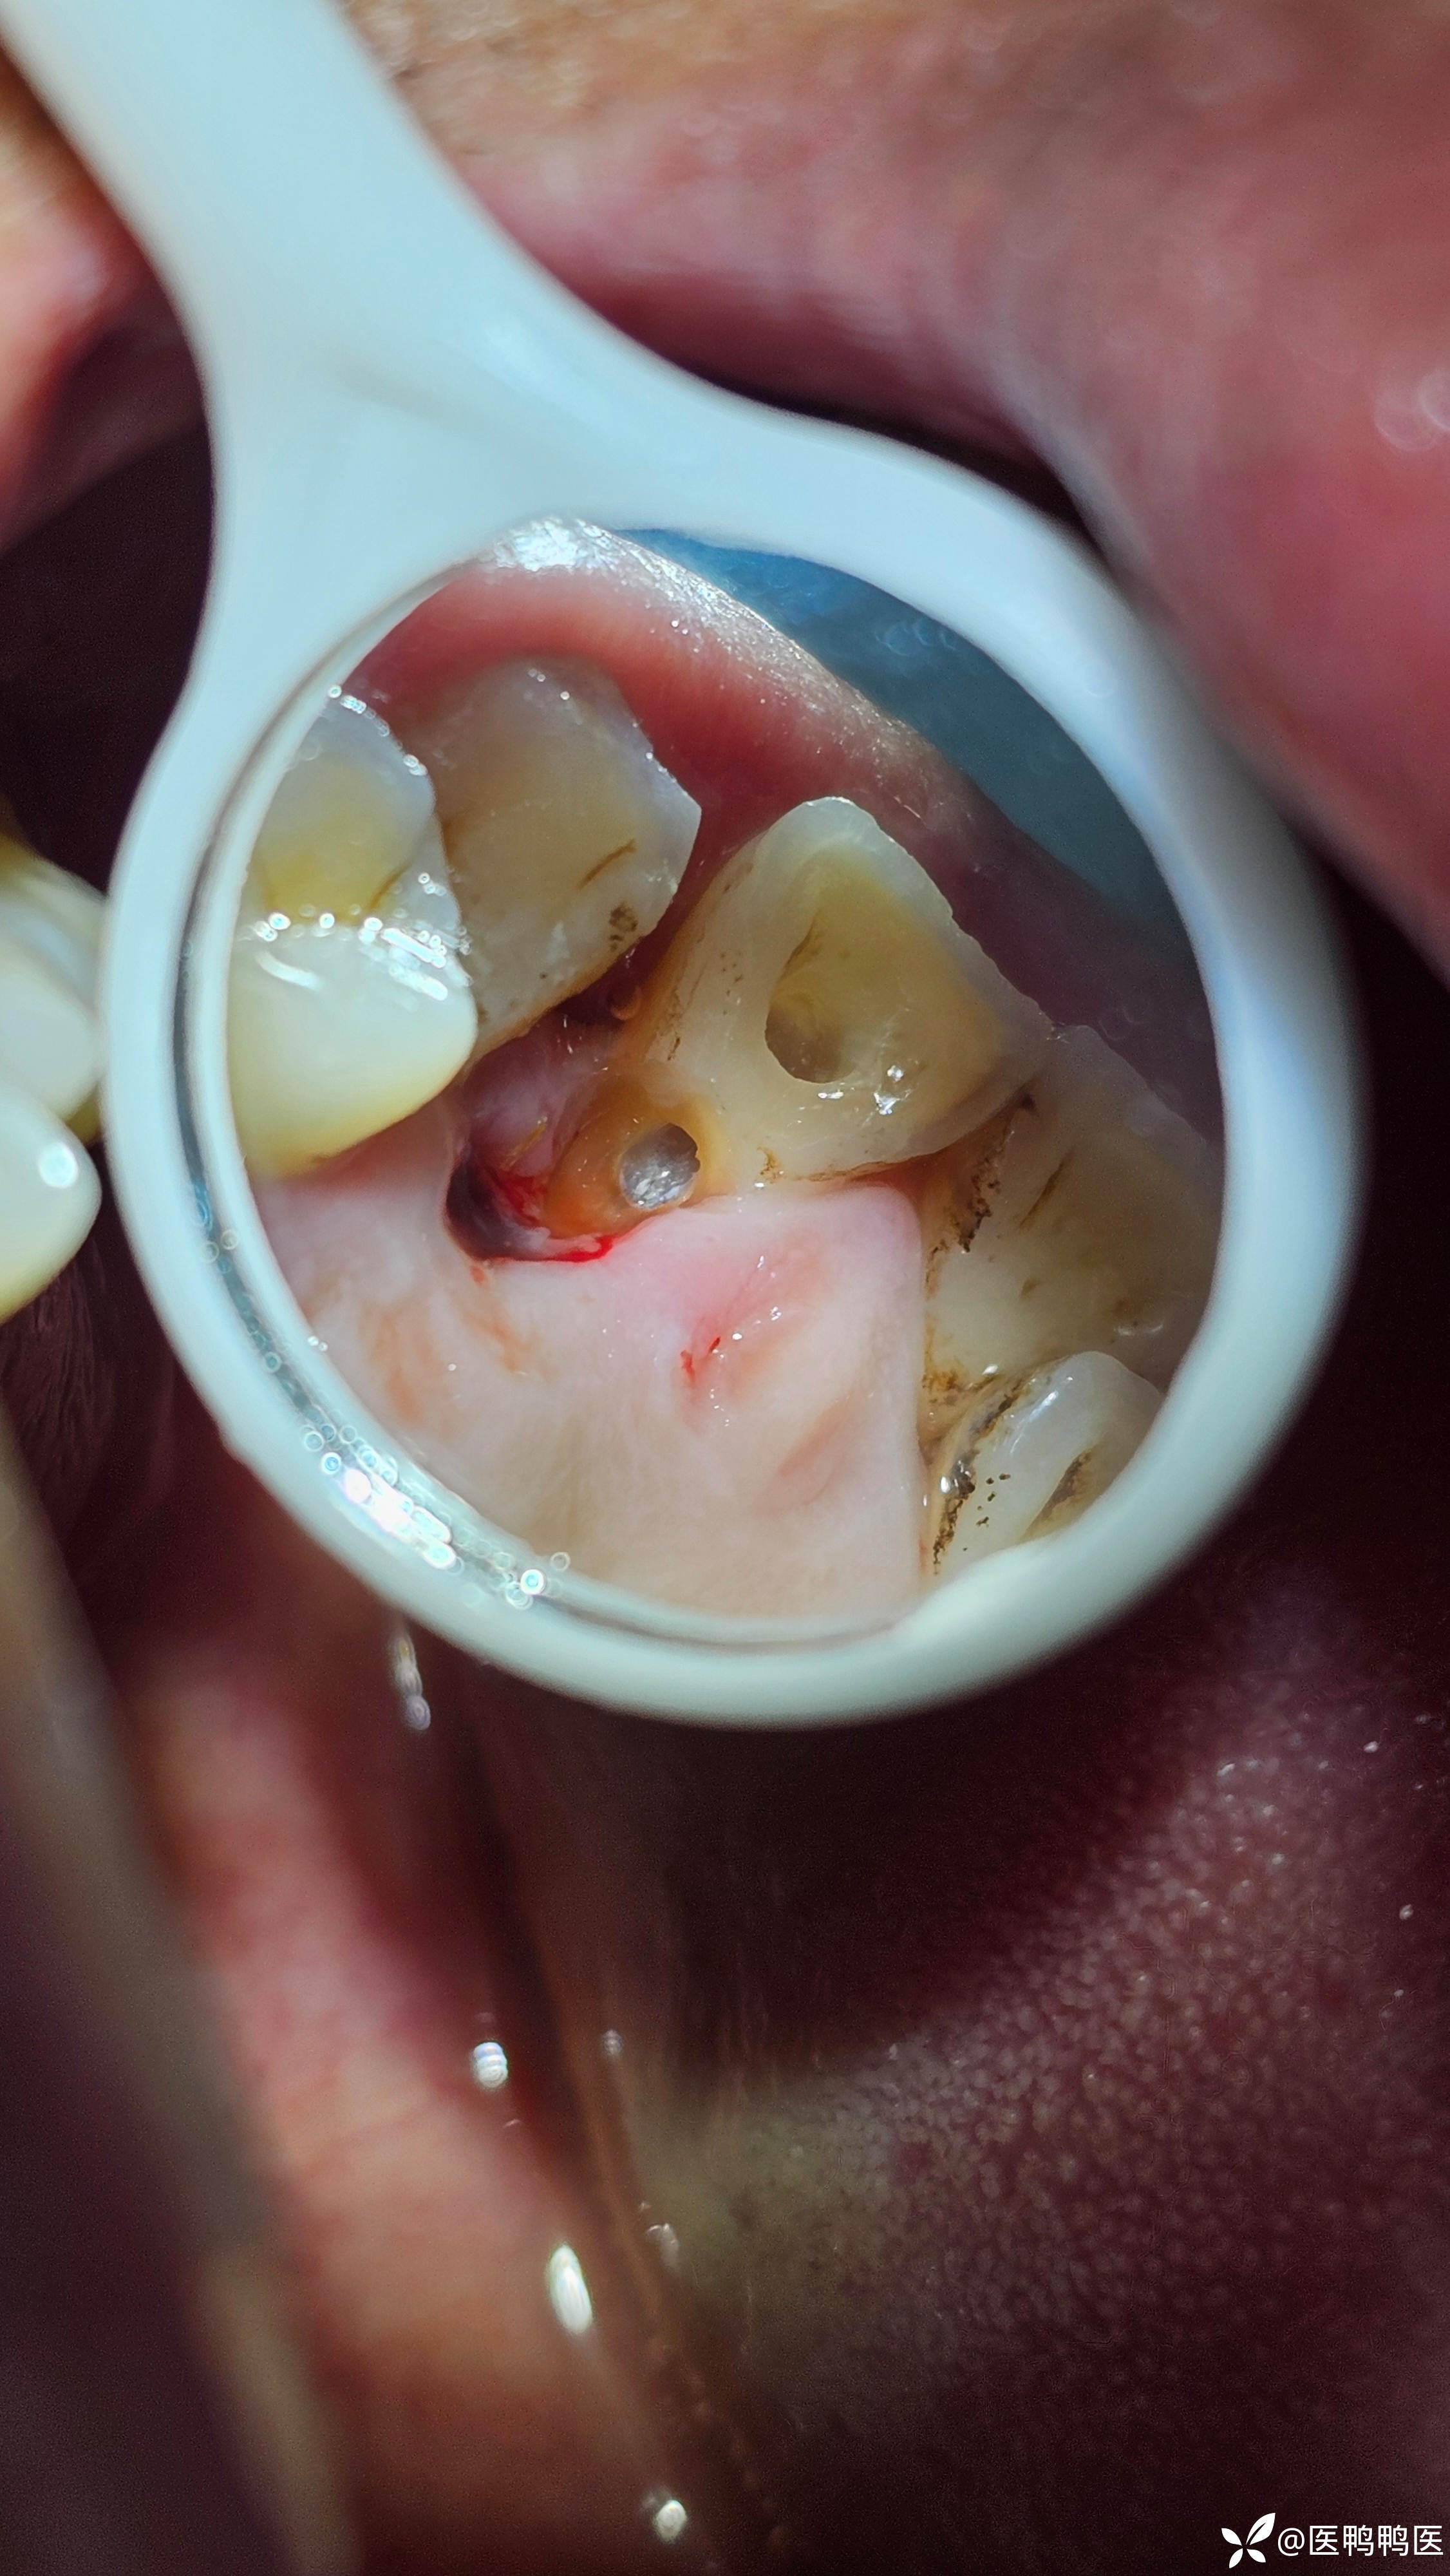

老板说留 就留吧 我是个以老板为主见的 有主见医生

情况就是这么个情况,具体情况还要看具体情况

告知患者只能看 不能用

龋齿 (53)